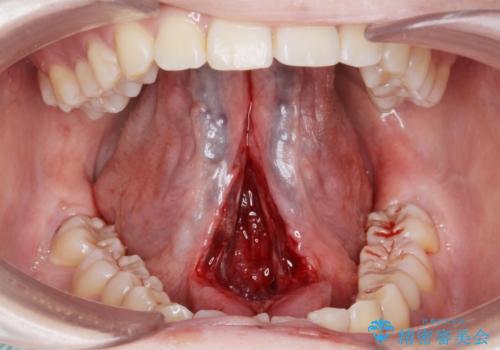

- 舌が動かしにくいとの事で来院。

局所麻酔を行い、舌小帯切除術を行いました。